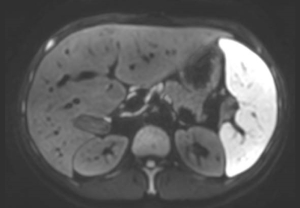

AI ベースの Philips SmartSpeed 再構成は、高速化技術の新たなベンチマークとなっています。この技術により Compressed SENSE があらゆる面で向上し、優れた画質と診断精度を維持しながらスキャン時間を短縮できます。"

Dr. Grisca Bratke

University Medical Center Cologne, Germany